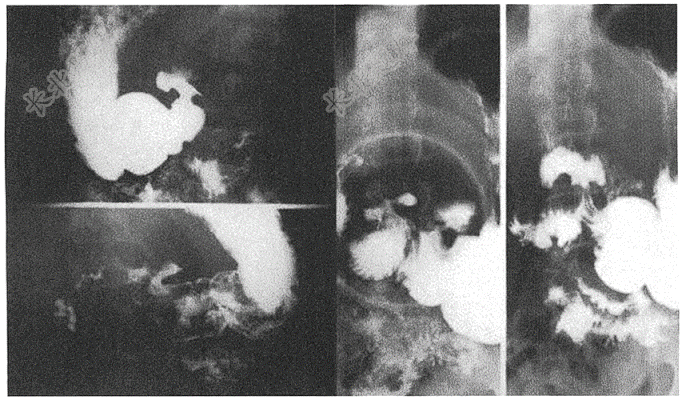

- 简答题患者,55岁反复腹痛2年,再发1周。